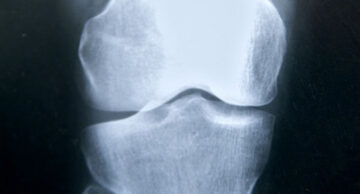

La osteoporosis produce fracturas que afectan hasta un 40% de las personas mayores de 50 años. Los bisfosfonatos se encuentran en la primera línea de tratamiento de la osteoporosis para evitar fracturas. Sin embargo, su uso se ha asociado a una fractura atípica de fémur según han descubierto, por primera vez, un equipo de científicos del Instituto Hospital del Mar de Investigaciones Médicas (IMIM) y de la Universidad de Barcelona. Este hallazgo, de gran trascendencia clínica, ha sido publicado en la revista The New England Journal of Medicine.

Un estudio exhaustivo de su genoma, mediante la técnica conocida como secuenciación completa del exoma, ha permitido hallar, por primera vez, una mutación común a las tres hermanas que podría explicar el por qué presentaron fractura atípica. Esta mutación daña una proteína (GGPPS) que forma parte de una cadena metabólica esencial para la salud ósea, que conocemos como vía del mevalonato. Se cree que esta mutación hace que el hueso sea vulnerable al fármaco y, en vez de fortalecerlo para evitar fracturas, lo hace más propenso a la fractura.